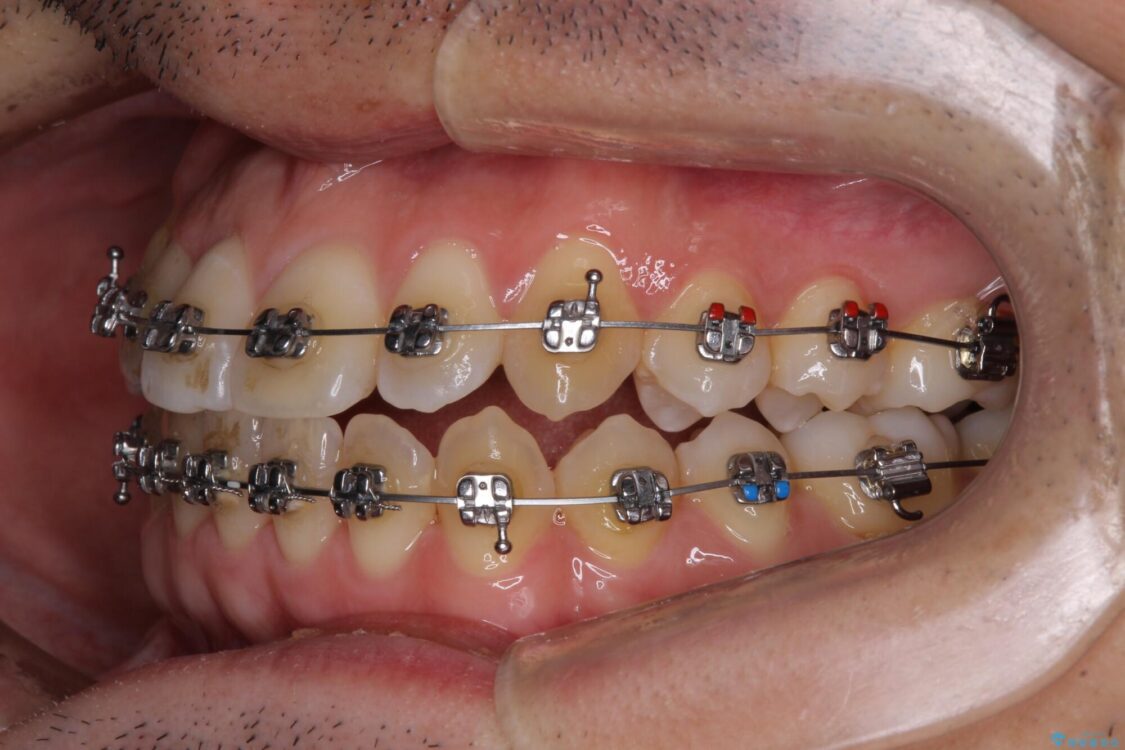

治療途中

• 左右の八重歯が気になる ワイヤー装置での咬み合わせ改善 治療途中画像